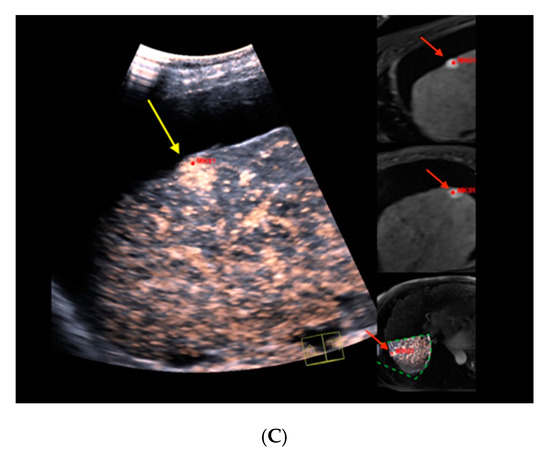

Figure 1 illustrates the MR-morphological correlate of a suspiciously hypervascularized focal liver lesion in a cirrhotic patient, which fusion imaging unraveled as underlying FNH.

Figure 1.

Real-time magnetic resonance imaging-/contrast-enhanced ultrasound (MRI-/CEUS)-fusion imaging of a hypervascularized focal liver lesion in a cirrhotic patient. (A) A hypervascularized subcapsular focal lesion in liver segment 7 was registered in MRI, arterial phase (left), a target lesion (MK01, red) was placed for precise correlation with native B-mode (right) in a side-by-side manner. The focal lesion otherwise was barely detectable by conventional ultrasound. (B) Additional Color Doppler showed livid hypervascularization of the lesion (right), a corresponding plane of MRI, arterial phase (left). (C) Peripheral-to-central contrast-enhancement and, finally, homogeneous contrast enhancement was registered in CEUS (left, maximized), implicating focal nodular hyperplasia. The software interface of the ultrasound device showed four different images: real-time CEUS images (left, maximized), MRI datasets in axial (upper right) and sagittal (middle right) reformation, and a real-time 3D navigation of the MRI-/CEUS-fusion imaging (lower right), (lesion marked by red arrows).